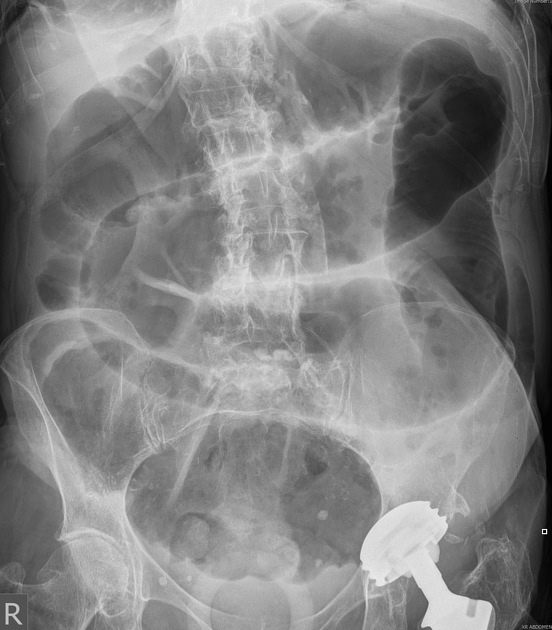

Findings on abdo x-ray of SBO

• Dilated bowel >3cm

• Central abdominal location

• Valvulae conniventes visible - complete lines crossing bowel

How well did you know this?

Abdo x-ray findings for LBO

• Dilated bowel >6cm or >9cm if caecum

• Peripheral location

• Haustral lines visible - not completely crossing bowel halfway haustra